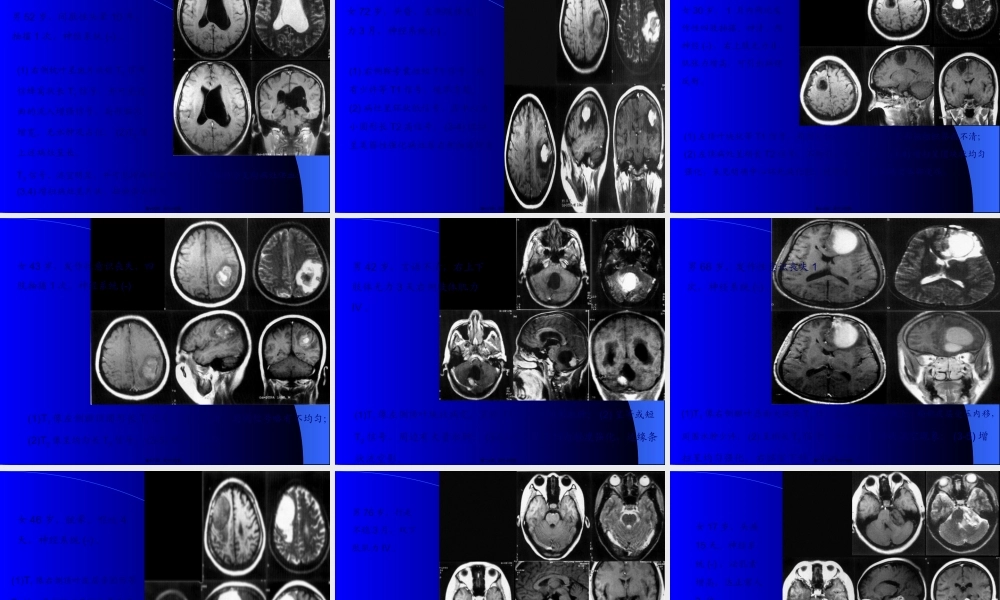

延髓颈髓蛛网膜下腔左侧椎动脉硬膜外脂肪第一页,共三十五页。女39岁,双上肢麻木,肉跳手变细2年。双上肢肌萎缩,肌力III-IV,颈5以下痛觉减低。T1小脑扁桃体及延髓下疝至颈椎管内颈3-胸4脊髓中央管扩张;FLASH(500/45/35)枕大池颅内外段消失,延髓中央管闭塞,颈1-2后纵韧带增厚钙化第二页,共三十五页。男55岁,左顶受击后头痛半月,以左侧面为主,无呕吐。体征:左侧面部角觉敏感。T1(360/11)左侧顶叶颅板下类梭形短T1病灶,皮质受压,脑室系统无改变,T2(2200/120)上述病灶呈长、短混杂改变。第三页,共三十五页。男59岁,急起双下肢无力三天,1月前有轻微头部外伤史。伸舌偏右,双下肢肌力IV,左侧上肢张力增高,左侧巴氏征(+)。T1(360/11)两侧额叶脑外大片长梭形短T1病灶,局部皮质受压,大脑纵短T1病灶;T2(2200/120)上述病灶呈长T2及混杂T2改变;T1(320/15)上述病灶呈短T1,两侧脑室、前角受压,变形,下移。第四页,共三十五页。女58岁,反复头痛伴双眼视力下降1年,左肢体无力三天。左侧中枢性面瘫,左上肢肌力III-IV。(1,2)T1(360/11)右侧额叶顶见大片低信号,脑组织介面不清;(3,4)T2(3300/120)上述病灶呈长T2信号;(5,6)增强T1(320/15)上述病灶呈不规那么脑回样、片状强化。第五页,共三十五页。男43岁,急起右侧肢体无力,言语不清1小时。神志清,右侧肢体肌力IV。(1,2)T1(360/11)左侧额顶颞叶顶见大片稍长T1信号,其间有小块状T1改变,占位效应显著,右侧脑室体旁小点状长T1信号;(3,4)T2(2200/120)上述病灶呈长T2信号,累及皮层。第六页,共三十五页。男58岁,急性头痛,言语不清2天。1年来反复发作;失语,伸舌偏右,右半身肌力差。(1,2)T1左颞枕叶大片长T1信号,左侧基底节点状长T1信号;信号;(3,4,5)T2像上述病灶呈长T2信号;诊断:左颞枕叶脑堵塞(陈旧性);左侧基底区腔隙性脑堵塞(病灶新)。第八页,共三十五页。男57岁,急起右侧肢体乏力伴意识不清12天。睁眼昏迷,右侧肢体肌力0。(1)T1左侧大脑半球有大片长T1信号,其中可见斑点状短T1信号,左侧面脑室轻度受压;(2)T2像上述病灶呈混杂T2信号;由于位于左大脑动脉分布区,堵塞后出血多为瘀斑状,无血肿中心,含铁血黄素沉着呈不规那么的点状。第九页,共三十五页。女69岁,渐起发呆半月,3天前言语不清、吞咽困难。神志欠清,右侧上下肢肌力差,病理反射(+)。(1,2)T1左侧颞叶有斑点状短T1信号及右侧基底区境界不清的稍长T1信号;(2)T2像上述病灶呈长T2信号;第十页...